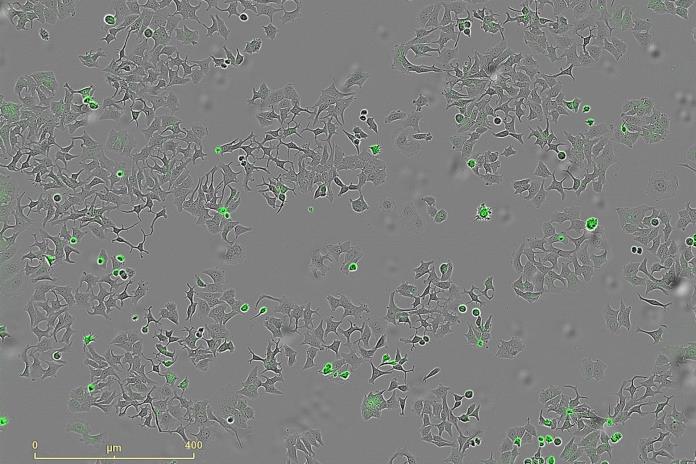

En la investigación han empleado sistemas avanzados de imagen en tiempo real que permiten contar células vivas y muertas, y medir la apoptosis (muerte programada) para observar con precisión el bloqueo de las vías.